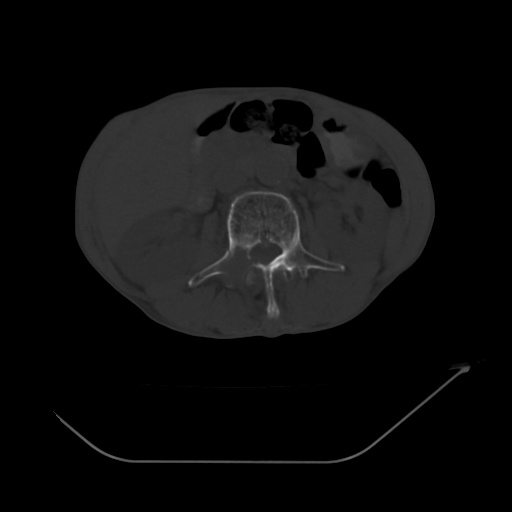

以下是引用zsl6918在2008-8-25 21:55:00的发言:[br]符合右肺周围性肺癌并肺内转移,左肺结核球。双肺肺气肿。腰椎附件转移。

以下是引用随光逐影在2008-8-25 22:03:00的发言:[br]1)考虑右肺下叶周围性肺癌并肺内转移,腰椎附件转移。2)左上肺结核(结核球形成)。3)双肺肺气肿(多发肺大泡形成)。4)双肺门区及纵隔内多发淋巴结钙化。

以下是引用qc80012345在2008-8-26 6:14:00的发言:[br]符合右肺周围性肺癌并肺内转移,左肺结核球。双肺肺气肿。腰椎附件转移。